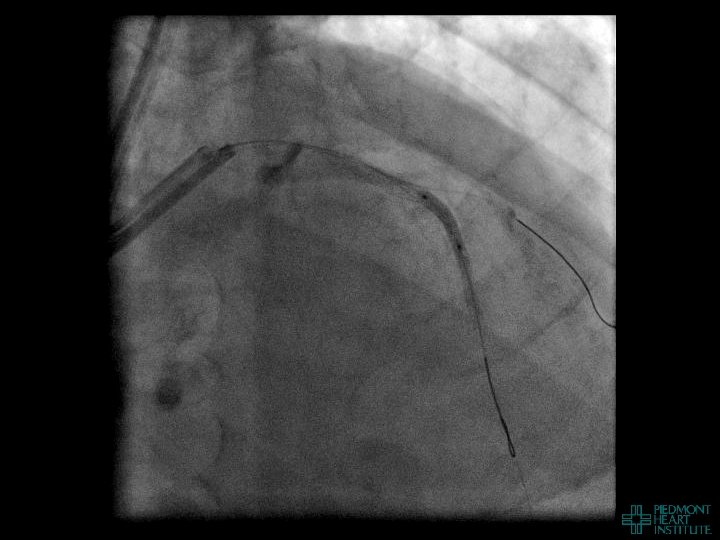

Coronary Perforation Methods of Patient Management • Dual Catheter (‘Ping Pong’) Technique • Prolonged

Coronary Perforation Methods of Patient Management • Dual Catheter (‘Ping Pong’) Technique • Prolonged balloon inflation and covered stents • Reversal of anticoagulation — Know contradictions to protamine sulfate for UFH; Avoid bivalirudin, LMWH — Reserve GP 2 b 3 a inhibition until successful crossing and wire change-out Embolization • — Coil, gelfoam, methacrylate, autologous blood/fat • Microcatheter Occlusion • Confirmation of successful management — Contralateral injection — Right heart catheterization — Echocardiogram — Contrast echocardiography